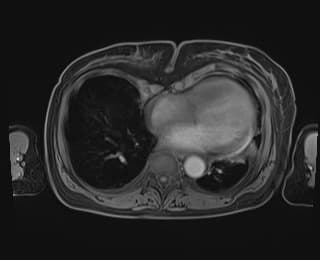

Axial C+ arterial phase

- Có vật chất tỷ trọng cao (high-density material) nằm trong túi mật (gallbladder) và ống mật chủ (common bile duct).

- Đi kèm với tình trạng dày thành túi mật không đều (gallbladder wall irregularly thickening) và thâm nhiễm mỡ xung quanh (surrounding fat stranding).

- Dấu hiệu căng phồng đáy túi mật (tensile gallbladder fundus sign) dương tính.

- Ghi nhận vài viên sỏi túi mật (gallbladder stones).

- Động mạch túi mật (cystic artery) xuất phát từ động mạch gan trái (left hepatic artery).

- Tại mức cổ túi mật (gallbladder neck), có một vùng tăng tỷ trọng dạng điểm (punctate hyperdensity) gợi ý có tổn thương động mạch túi mật.

THẢO LUẬN: Sự hiện diện của máu trong túi mật và ống mật chủ cùng với thành túi mật dày không đều gợi ý chẩn đoán viêm túi mật xuất huyết (hemorrhagic cholecystitis), một biến chứng hiếm gặp của viêm túi mật cấp (acute cholecystitis). Vùng tăng tỷ trọng dạng điểm của động mạch túi mật gợi ý tình trạng giả phình động mạch túi mật (cystic artery pseudoaneurysm). Bệnh nhân đã được phẫu thuật và chẩn đoán viêm túi mật xuất huyết đã được xác nhận.